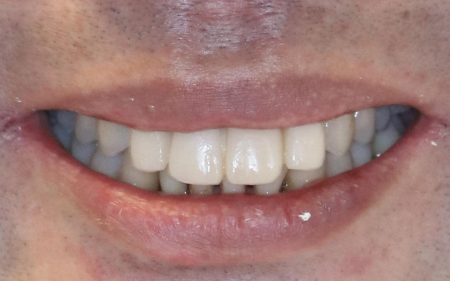

治療後

また、最終的な被せ物に仮歯の形を反映させるため、被せ物を作製する「ラボ」にて仮歯の形をデジタルスキャンし、自然な白さの被せ物「ジルコニアブリッジ」を作製しました。

完成したジルコニアブリッジを実際に装着して噛み合わせを調整し、エアーフローで接着面を清潔にした後に、歯科用の接着剤「ジーセムone」で接着して治療を終了しました。